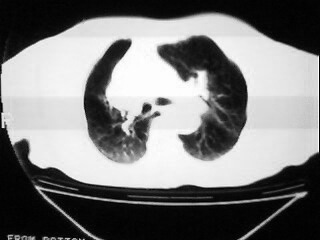

女,79,咳 嗽月余,无其它不适

1)两肺炎症。2)食管裂孔疝可能;建议行上消化道钡餐检查。

后纵隔内左心房至肝左叶后方椎体中线偏左巨大软组织包块,其壁均匀比较薄,其内可见宽气液平。

考虑食管裂孔疝。建议钡餐检查